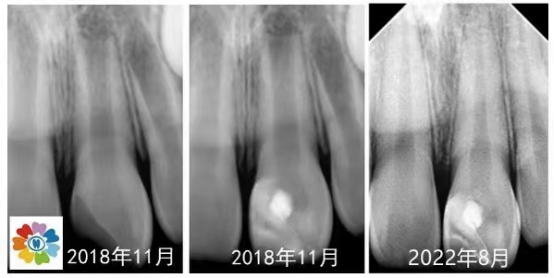

手动锉的探查与疏通 根管长度与根管预备长度的确定 根管预备的宽度确定 根管预备的逐步后退法 根管预备的冠向下法 弯曲根管的预备方法 根管化学预备的常用药物及浓度 化学预备的器械与药物使用步骤 实操:在透明模块和离体牙上实操镍钛锉根管预备

常用根管封药及选择 根管封药与难治性根尖周炎的控制 合适主尖的确定 常用根管糊剂的特性及选择 单尖法根管充填步骤方法 热牙胶垂直加压技术 热牙胶连续波技术 实操:老师在模型上示教单尖法及热牙胶充分步骤方法,学员同步实操。